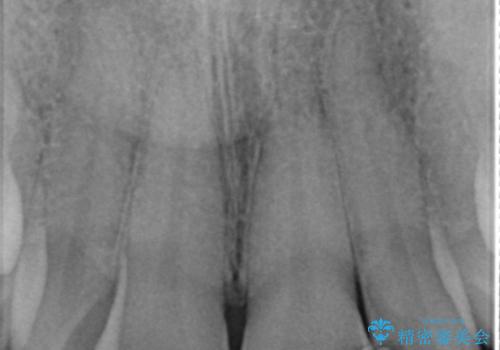

- 前歯のプラスチックの詰め物が気になると来院された患者様です。

左上の前歯に詰められたプラスチック(コンポジットレジン)は、劣化し変色していました。

レジンを除去したところ二次う蝕を認めたため、丁寧に虫歯をとりました。

歯の欠損範囲が大きいことから、同様にレジン修復しても欠けやすいためセラミッククラウンによる補綴を行いました。